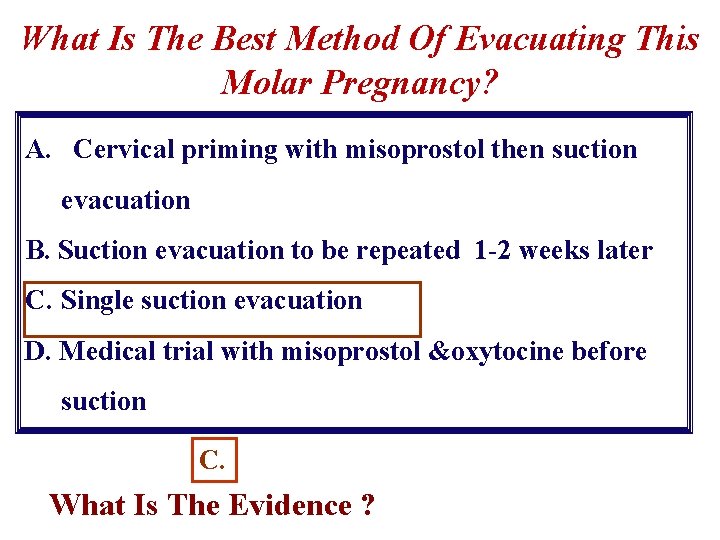

What Is The Best Method Of Evacuating This Molar Pregnancy? A. Cervical priming with misoprostol then suction evacuation B. Suction evacuation to be repeated 1 -2 weeks later C. Single suction evacuation D. Medical trial with misoprostol &oxytocine before suction C. What Is The Evidence ?

What Is The Best Method Of Evacuating A Molar Pregnancy? For Complete mole is: Suction curettage Cervical preparation with prostaglandins or misoprostol , should be avoided to reduce the risk of embolisation (No sufficient studies) RCOG Guideline No. 38 ; 2010